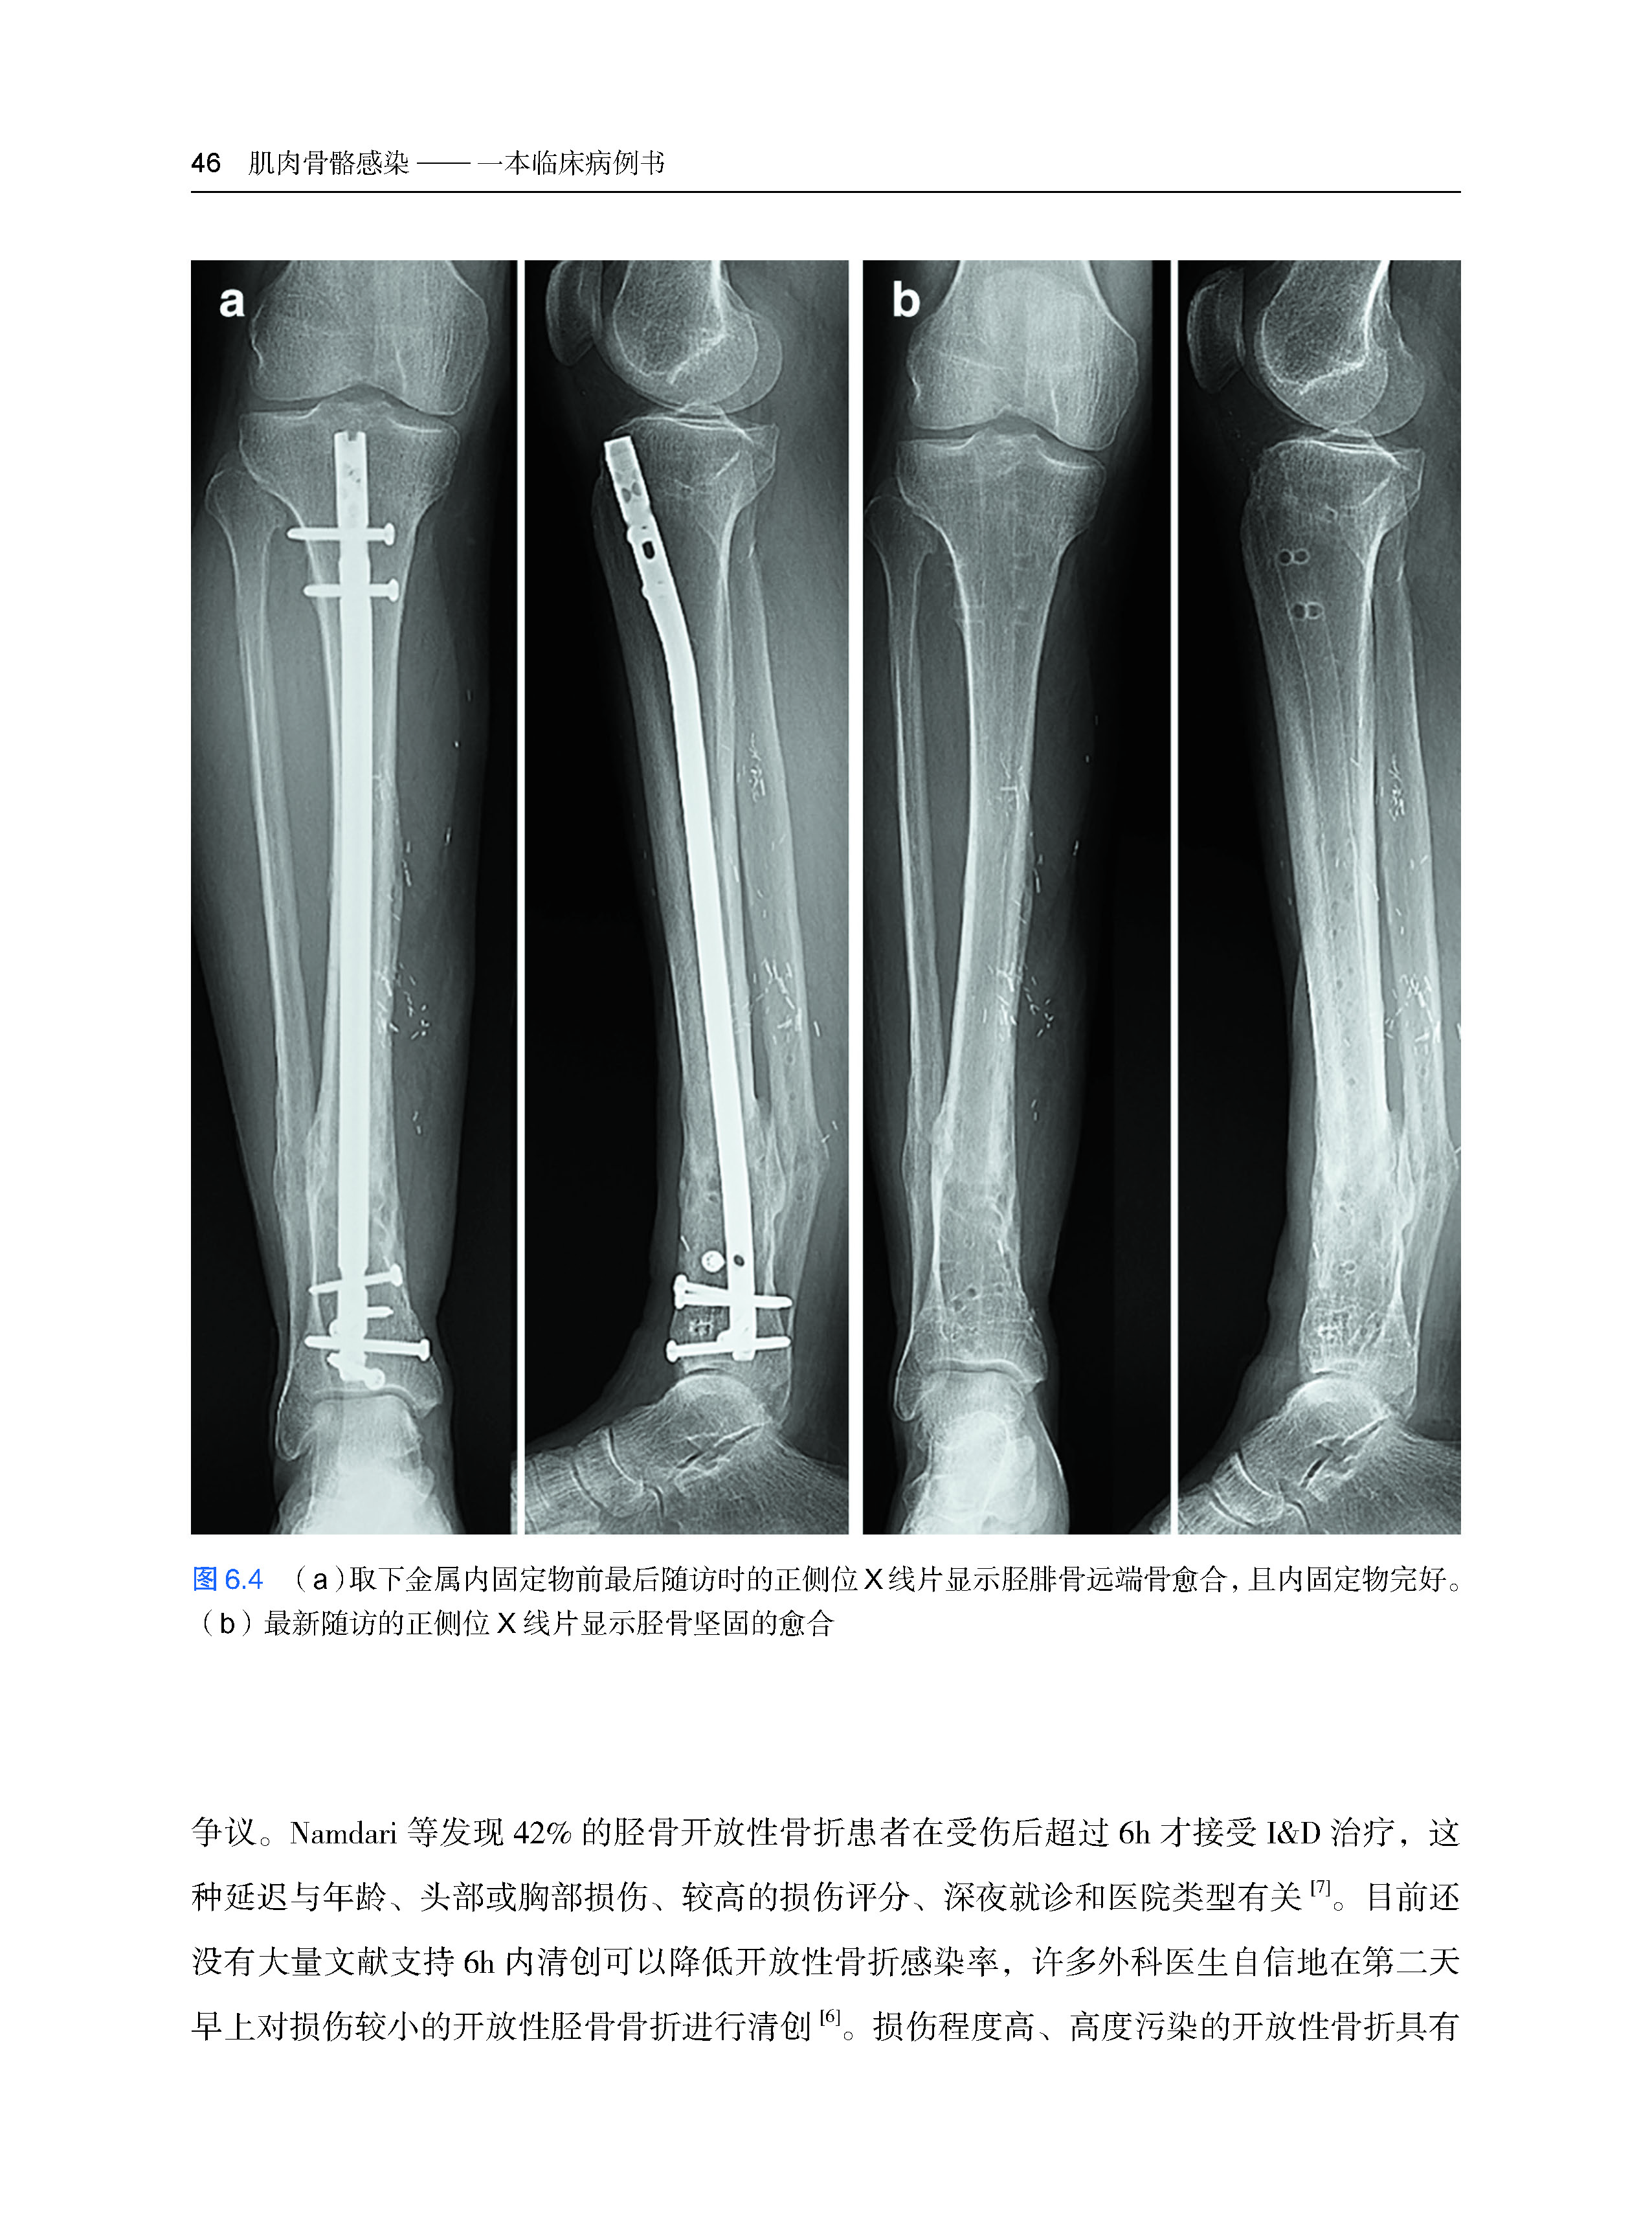

第六章 胫骨感染性骨不连